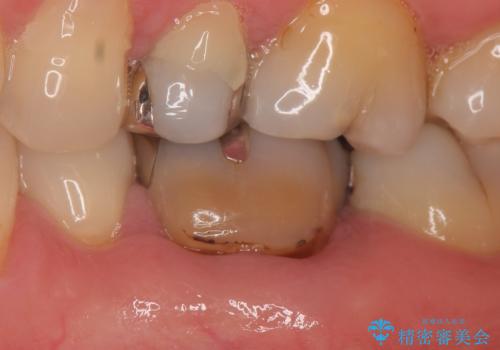

- 他院にて左下6の再根管治療を勧められ当院にいらっしゃった方の症例です。

再根管治療終了後、オールセラミッククラウンにて補綴を行いました。

今回用いたオールセラミッククラウンはジルコニアフレームという白い素材の上にセラミックを盛っているため、審美性が非常に高いのが特徴です。

また、ジルコニアは人工ダイヤモンドの材料にも使われているほど高い強度を持っており、そのためオールセラミッククラウンは審美性だけでなく、奥歯やブリッジの補綴も可能とするクラウンです。